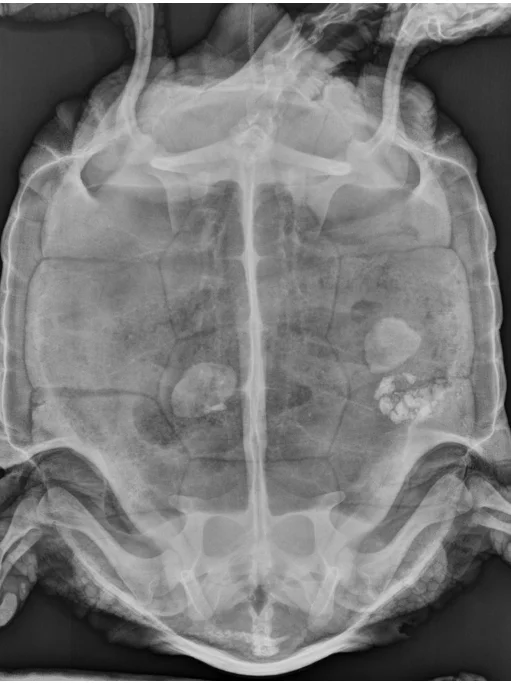

UC Exotic Team Treats 61-Year-Old Tortoise